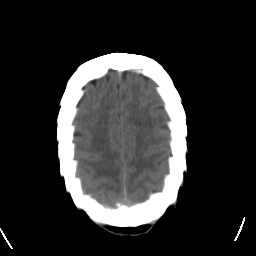

Stroke CT #3 -- Slice #20

[Home][Help][Clinical] Slice 20